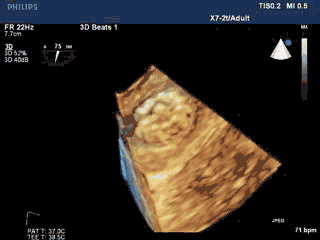

术中TEE双平面及DSA造影显示,梳状肌发达,延伸至心耳口部。

DSA造影显示LAA开口直径18mm,深26mm,拟采用24mm Watchman封堵器。